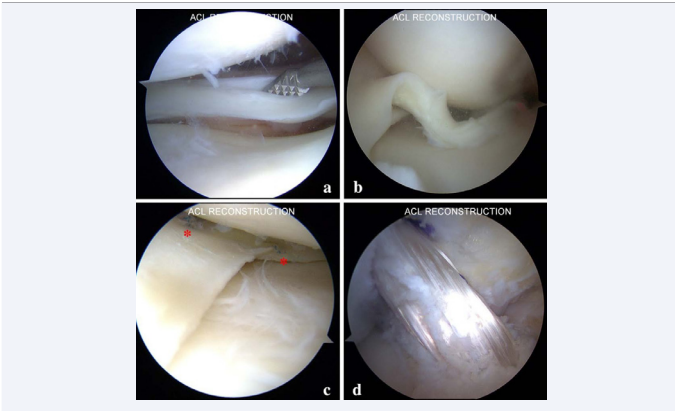

Arthroscopic knee surgery is therapeutically indicated for meniscal, ligamentous, patellofemoral, neoplastic, loose body, arthritic, cartilage conditions, and fractures, at the same time providing diagnostic value for additional lesions. Meniscal procedures can be menisectomy or repair. Anterior and posterior cruciate ligament reconstruction is a standard procedure supported by evidence with clearly defined indications. Patellofemoral procedure is mainly for patellar instability. Chondral procedure including debridement, micro-fracture and osteochondral transplantation have weaker evidence of support for degenerative conditions [37-40] (Figure 4)

Figure 4 Application of knee arthroscopy (a) Longitudinal meniscal tear. (b) Bucket-handle meniscal tear. (c) Meniscal repair with all-inside suture technique (asterisk). (d) ACL reconstruction with satisfactory tension of the graft.

Figure 4 Application of knee arthroscopy

(a) Longitudinal meniscal tear.

(b) Bucket-handle meniscal tear.

(c) Meniscal repair with all-inside suture technique (asterisk).

(d) ACL reconstruction with satisfactory tension of the graft.